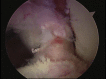

Posterior shoulder dislocation is an unusual injury often associated with electrical shock or seizure. As with anterior instability, patients frequently present with an impaction injury to the anterior aspect of the humeral head known as a "reverse Hill-Sachs lesion." The treatment of this bony defect is controversial, and multiple surgical procedures to fill the defect in an effort to decrease recurrence have been described. Most of the reports have focused on an open approach using variations of lesser tuberosity and subscapularis transfers, bone allograft, and even arthroplasty to assist with persistent instability. We advocate an arthroscopic technique that involves a suture anchor-based distal tenodesis of the subscapularis tendon or a reverse remplissage procedure.